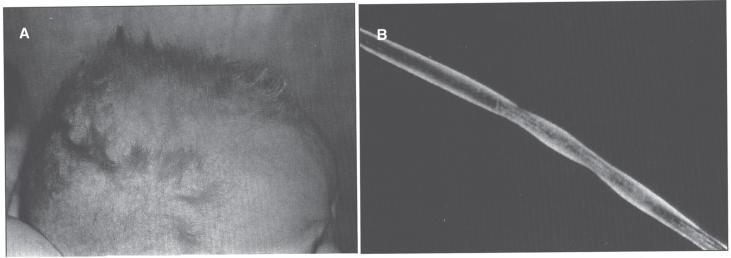

Trace elements are chemical elements needed in minute amounts for normal physiology. Some of the physiologically relevant trace elements include iodine, copper, iron, manganese, zinc, selenium, cobalt and molybdenum. Of these, some are metals, and in particular, transition metals. The different electron shells of an atom carry different energy levels, with those closest to the nucleus being lowest in energy. The number of electrons in the outermost shell determines the reactivity of such an atom. The electron shells are divided in sub-shells, and in particular the third shell has s, p and d sub-shells. Transition metals are strictly defined as elements whose atom has an incomplete d sub-shell. This incomplete d sub-shell makes them prone to chemical reactions, particularly redox reactions. Transition metals of biologic importance include copper, iron, manganese, cobalt and molybdenum. Zinc is not a transition metal, since it has a complete d sub-shell. Selenium, on the other hand, is strictly speaking a nonmetal, although given its chemical properties between those of metals and nonmetals, it is sometimes considered a metalloid. In this review, we summarize the current knowledge on the inborn errors of metal and metalloid metabolism.

微量元素是正常生理功能所需的微量化学元素。一些与生理相关的微量元素包括碘、铜、铁、锰、锌、硒、钴和钼。其中,有些是金属,特别是过渡金属。原子的不同电子壳层具有不同的能级,最靠近原子核的电子壳层能量最低。最外层电子的数量决定了该原子的反应活性。电子壳层又分为子壳层,特别是第三壳层有s、p和d子壳层。过渡金属被严格定义为原子具有不完全d子壳层的元素。这种不完全的d子壳层使它们易于发生化学反应,特别是氧化还原反应。具有生物学重要性的过渡金属包括铜、铁、锰、钴和钼。锌不是过渡金属,因为它有一个完整的d子壳层。另一方面,严格来说硒是一种非金属,尽管鉴于其化学性质介于金属和非金属之间,它有时被视为类金属。在本综述中,我们总结了目前关于金属和类金属代谢先天性缺陷的知识。